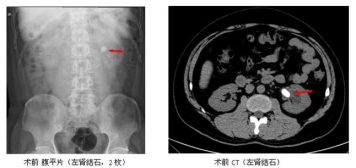

经皮肾镜碎石术是将肾镜通过皮肾通道(一条经皮肤穿入肾盂肾盏内的通道)进行体内碎石和取石的现代外科微创技术。适应于体积较大(通常直径大于2厘米)的肾结石和输尿管上段结石。经皮肾镜碎石术是目前处理肾和输尿管上段体积较大结石的最理想的方法。